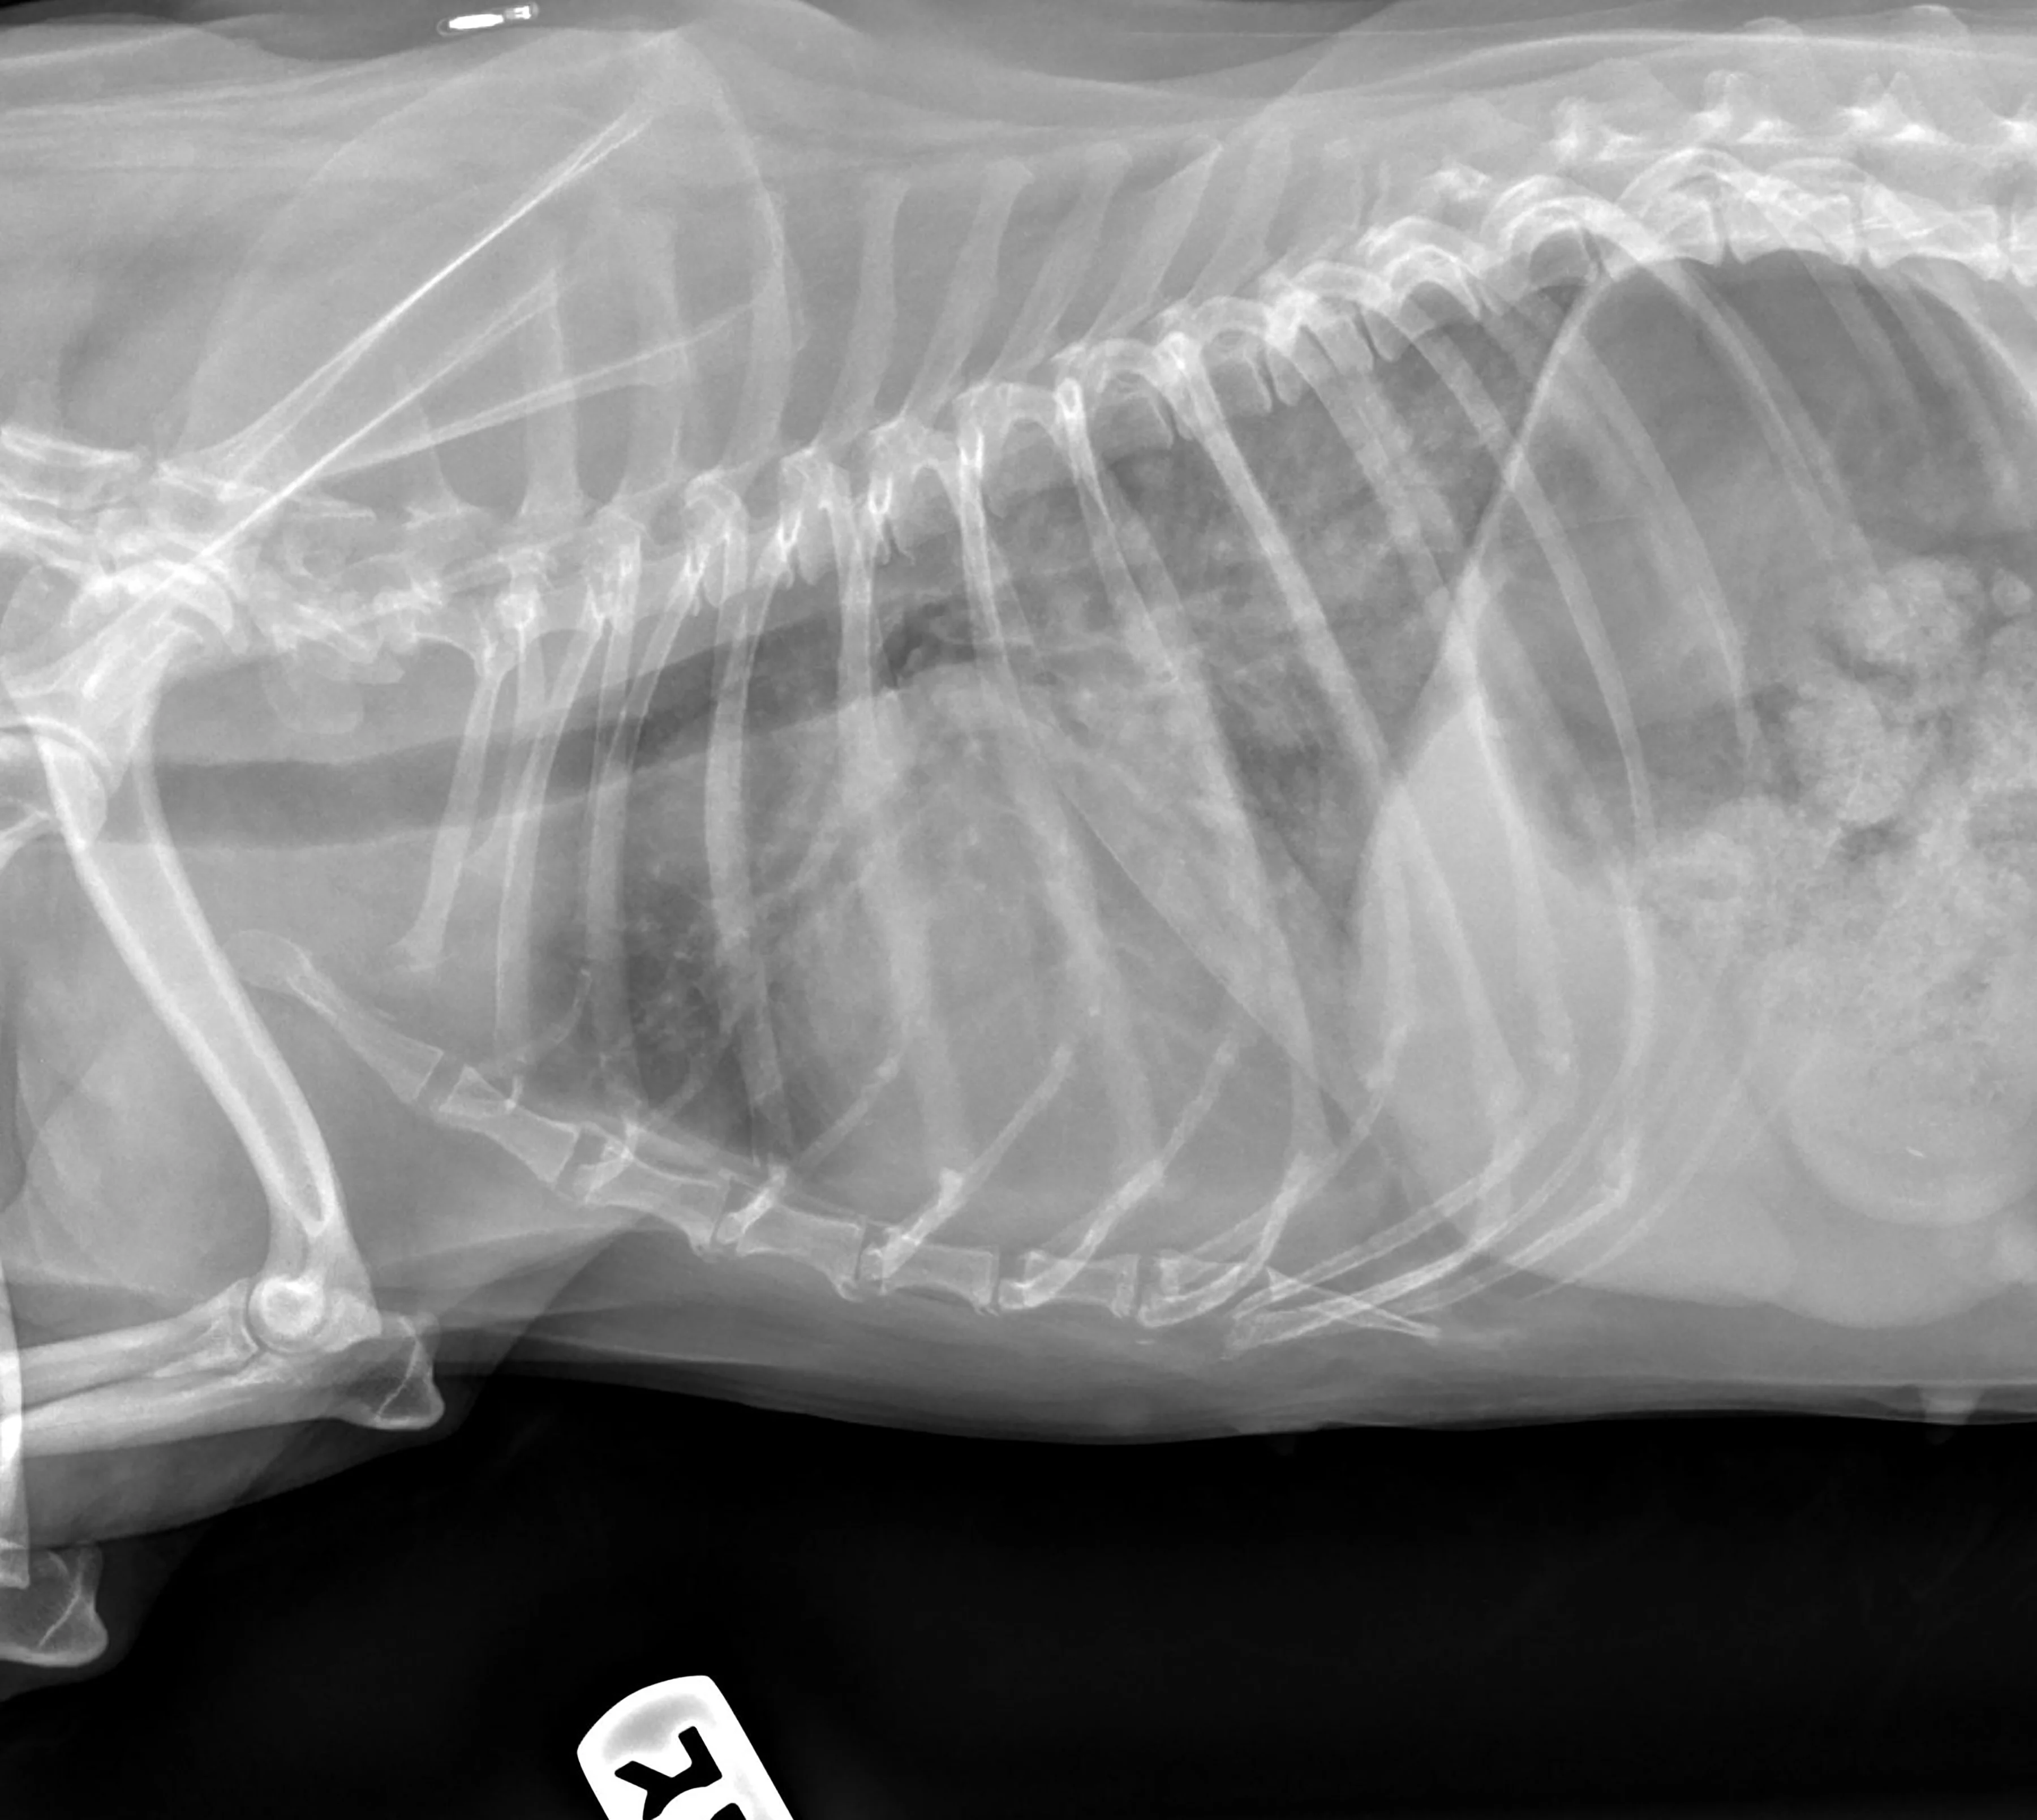

Ziggy, a 22-lb (10-kg) 14-year-old neutered male crossbreed dog, is presented for fever and a firm, painful swelling ventral to the right eye. Stage C myxomatous mitral valve disease (MMVD) had been diagnosed previously, and he was recently treated for congestive heart failure (CHF)(Figure 1). Pimobendan (0.5 mg/kg PO total daily dose divided and administered every 12 hours) and furosemide (2 mg/kg PO every 12 hours) were administered, and recheck radiographs revealed normal pulmonary parenchyma.

Radiograph revealing cardiomegaly and perihilar pulmonary edema indicative of CHF